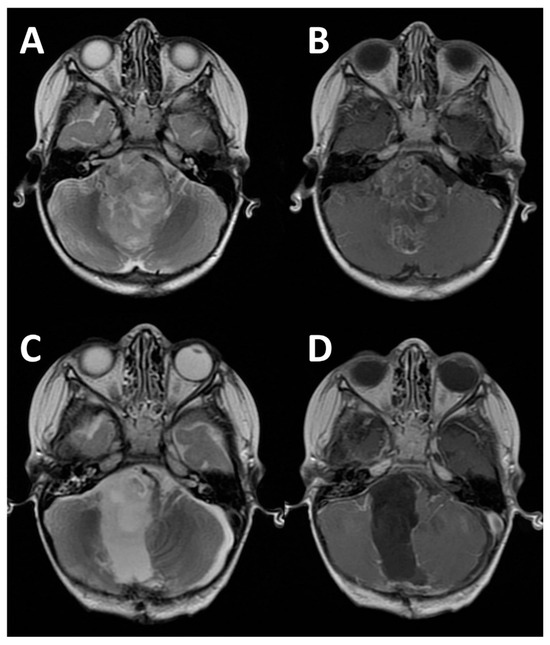

Cerebello-Pontine Angle Tumors in Children: An Update on Challenging Neoplasms

by Luca Massimi, Giuliano Di Monaco, Jacopo Ciccani, Federico Bianchi, Paolo Frassanito and Gianpiero Tamburrini

Diagnostics 2026, 16(1), 131; https://doi.org/10.3390/diagnostics16010131 - 1 Jan 2026

Introduction: Cerebellopontine angle (CPA) tumors are rare in children. As a result, knowledge on them is still limited, often concerning old series. The goal of this study is to provide an update on these challenging neoplasms by presenting a large series compared with [...] Read more.

Introduction: Cerebellopontine angle (CPA) tumors are rare in children. As a result, knowledge on them is still limited, often concerning old series. The goal of this study is to provide an update on these challenging neoplasms by presenting a large series compared with those available in the literature and focusing on tumor characteristics, molecular pattern, extent of tumor removal, surgical complications, and outcome. Methods: All children with CPA tumors consecutively operated on between 2010 and 2020 (minimum follow-up: 5 years) and with complete follow-up data were considered. Retro-sigmoid approach was used for tumors arising from CPA (group A) while a midline sub-occipital was used for those extending into CPA (Group B). Intraoperative neuronavigation, neuro-monitoring, and ultrasounds were routinely utilized. Results: 48 children (54 tumors) were included (mean age at surgery: 6.9 years, 38% infants, M/F ratio 1.1). Hydrocephalus was present at diagnosis in 27% of cases. Gross total resection of the tumor was obtained in 59% of cases, and subtotal and partial resection in 24% and 17%, respectively. Complications occurred in 25% of cases. Group A was composed of 23 children: the most common tumor was schwannoma (43%) followed by ependymomas, medulloblastoma, AT/RT (13% each), and less common histotypes. Group B was composed of 25 children: ependymomas (60%), AT/RT (20%), medulloblastoma (12%), others (8%). All but one ependymomas belonged to PF-A molecular group, while medulloblastomas were equally divided between WNT and Sonic-Hedgehog. The overall survival rate after a mean 7.2-year follow-up is 71%. A total of 14 patients died because of tumor or disease progression. No statistical differences between the two groups were detected as far as demographic data, tumor growing pattern, extent of tumor removal, complication rate, and overall survival were concerned. Only the mean tumor diameter was significantly longer in group B (3.9 cm vs. 3.3 cm). Apart from some differences in the demography, the extent of tumor removal and complications, no relevant differences were noticed among the series analyzed. Conclusions: Pediatric CPA tumors are uncommon but not rare and present significant management challenges. Surgery is demanding. The long-term survival is poorly improved compared with the past and compared with other posterior fossa tumors, the prognosis is mainly related to the biological tumor characteristics and the adjuvant treatments rather than the surgical excision. Full article